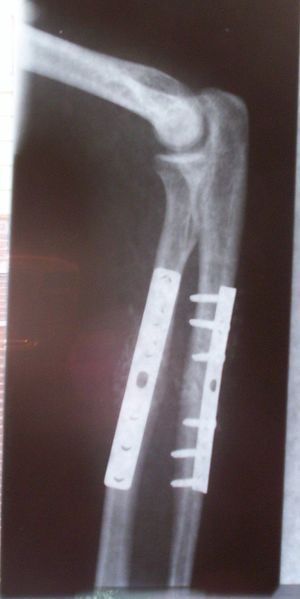

طب العظام يعنى بشكل عام بتصحيح الكسور جراحيا وتجبيرها إضافة إلى عمليات إصلاح وتبديل المفاصل التالفة. بالإضافة إلى أنواع أخرى من العمليات الجراحية التي تعالج أمراض العظام والجهاز الحركي.

- رفع المثبتات الداخلية (من شرائح ومسامير وغيرها).

- علاج كسور عظمتي الزند والكعبرة.